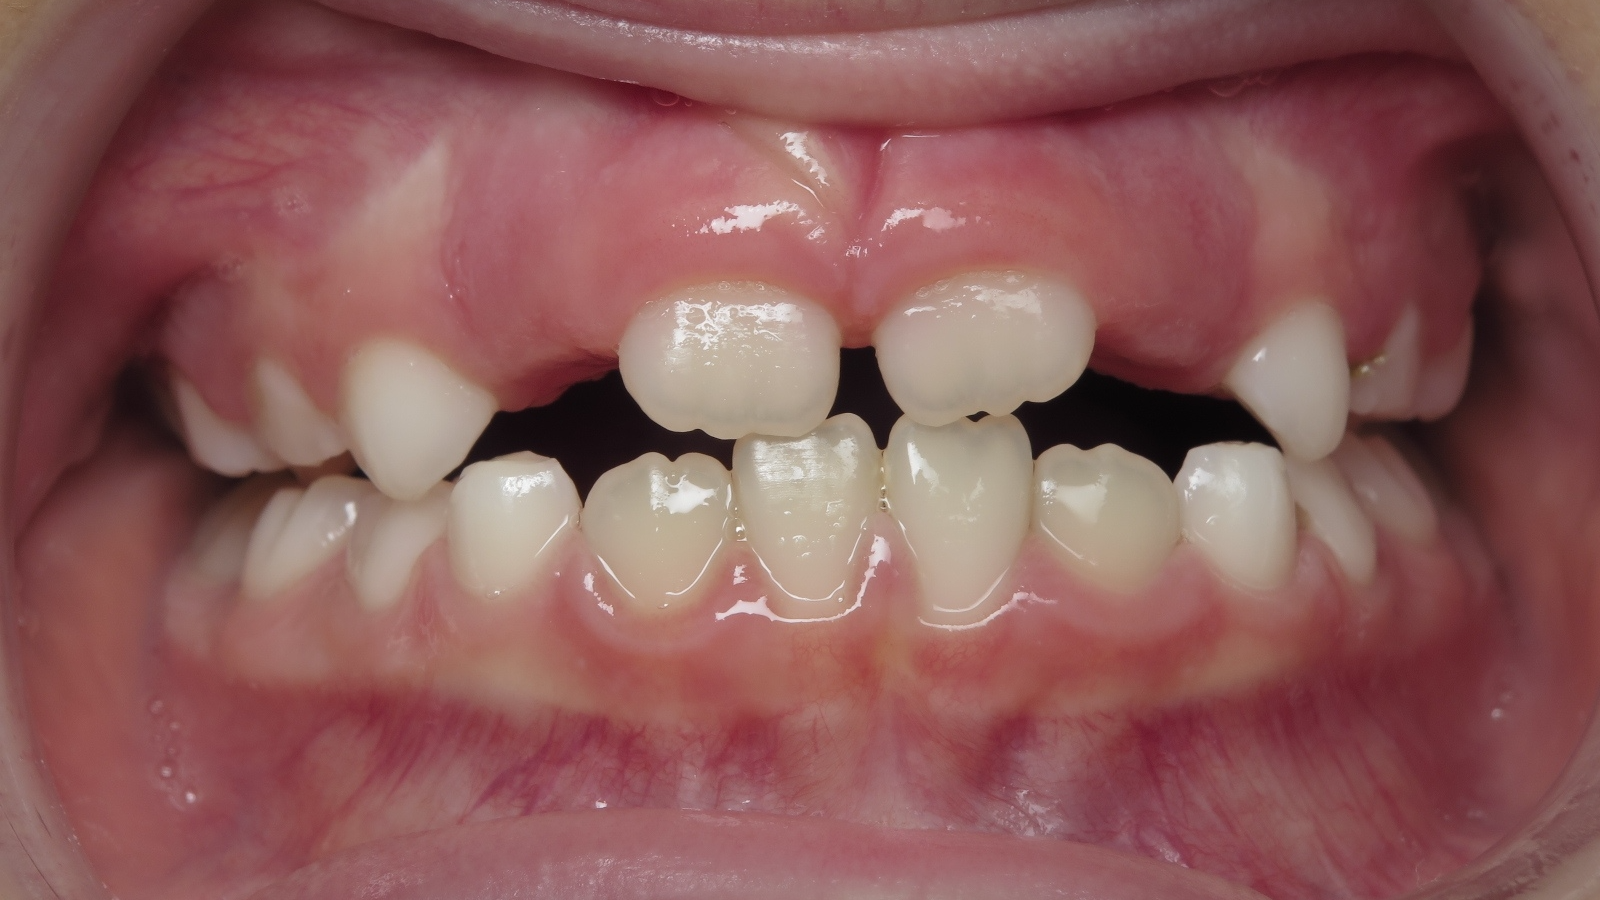

25. bout à bout anterieur 6 ans

dents du haut bout à bout par rapport à celle du bas